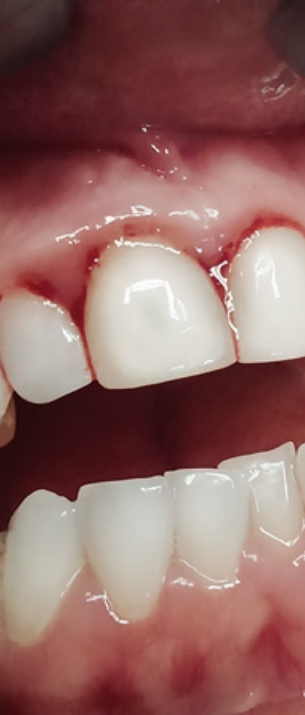

첫번째 치은염 증상은 바로

잇몸의 붓기와 출혈이였어요.

두번째 증상은 잇몸이 붉게 변하며

붓기가 생기는것인데요.

건강한 잇몸은 연분홍색을 띄며,

잇몸에 염증이 발생하면 빨갛게

부워오르게 된다고 했어요.

이러한 경우 잇몸이 예민해져 있어

살짝만 칫솔로 건드려도 출혈이 쉽게

발생하며 통증 또한 느껴질 수 있는

부정적인 상태에 해당됐어요.

치태나 치석은 치실이나 일반 칫솔질만으로

쉽게 제거가 되지 않기 때문에

치과에 방문하여 치아 스케일링을

통해 제거해주는 과정이 필요했어요.